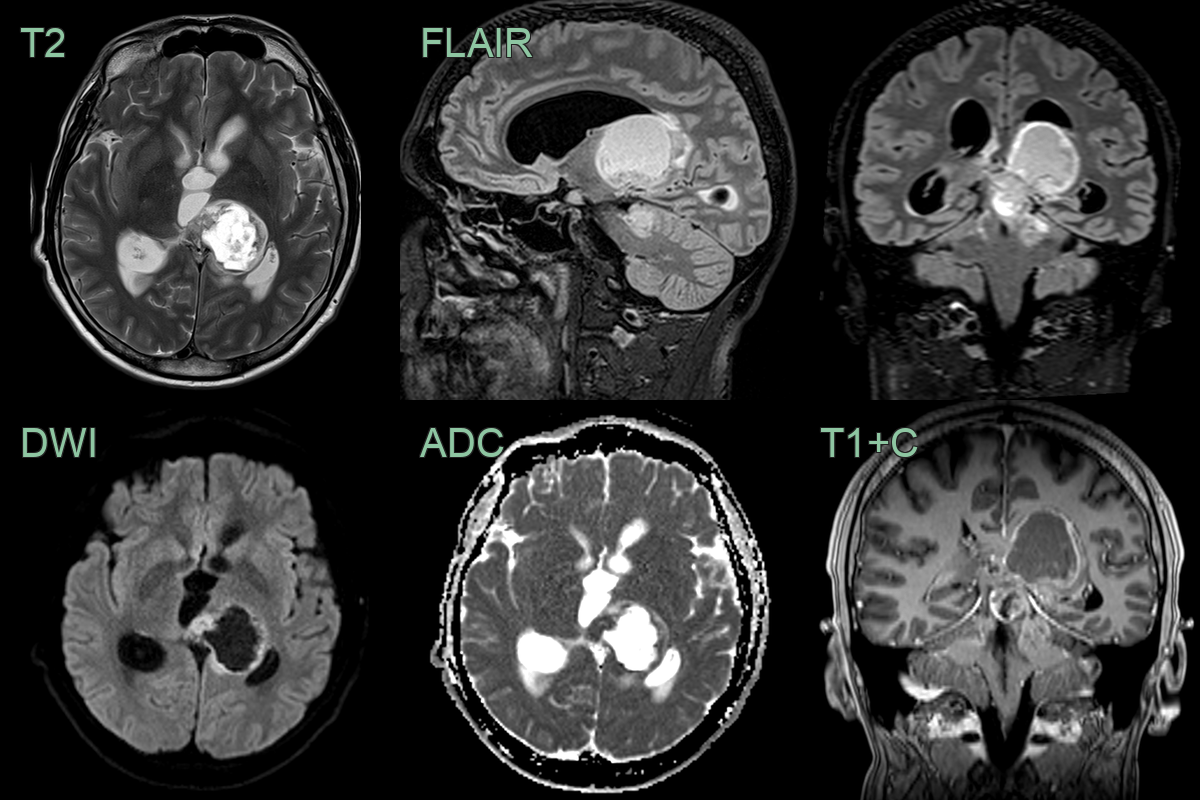

- 20-year-old patient presented with acute onset headache.

- MRI showed a acute obstructive hydrocephalus secondary to a solid-cystic lesion centred on the left thalamus.

- Low ADC values within the solid and enhancing component of the tumor indicated hyperceullarity.

- Biopsy revealed a H3 K27M-mutant diffuse midline glioma.